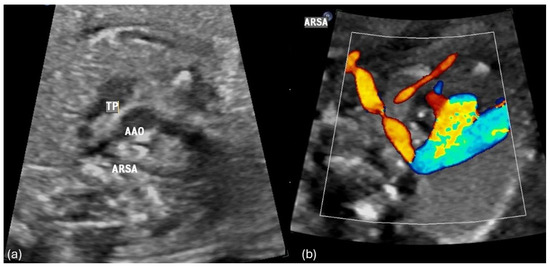

4.1. AAA Diagnostics of AAA and Accuracy Rate